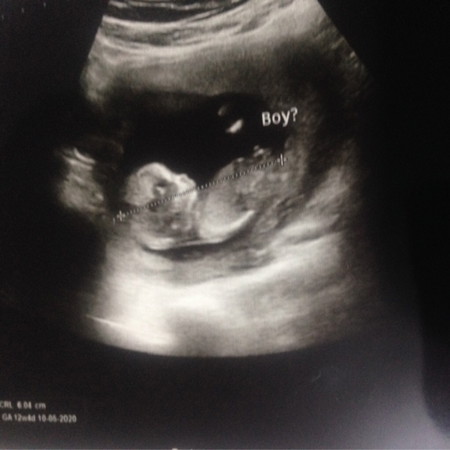

คุณแม่รู้เพศลูกกันตอนกี่เดือน ค่ะ..รูปนี้ล่าสุดวันนี้เองค่ะ คุณหมอบอกยังไม่100% แต่แปลกแค่3เดือนทำไมเหมือนจะเห็นชัด คุณหมอเลยให้ Boy ไว้ก่อนค่ะ (เห็นชัดมั้ยค่ะจู๋น้อง) คุณหมอบอกเด็กนอนหงายเลยเห็นชัดค่ะ